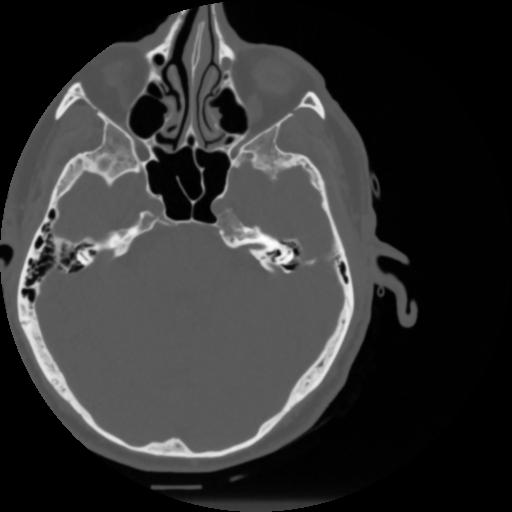

4 CEREBRO,,Vol,0.5,CEREBRO,,